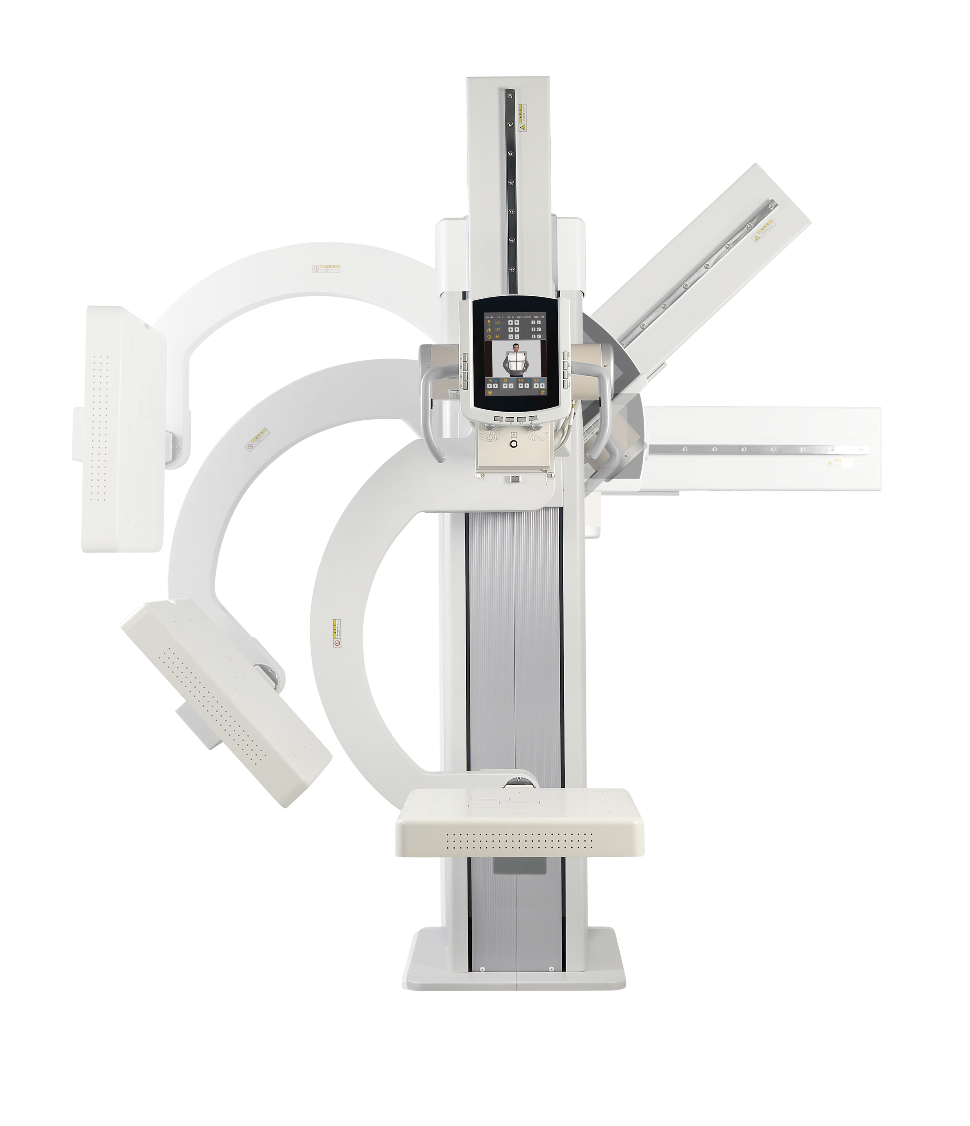

Intermedical est une société italienne spécialisée dans la conception et la fabrication de systèmes de radiologie mobiles et fixes. Elle met l’accent sur l’innovation et les technologies numériques modernes afin d’offrir des solutions d’imagerie précises, fiables et simples d’utilisation pour les hôpitaux et centres médicaux du monde entier.